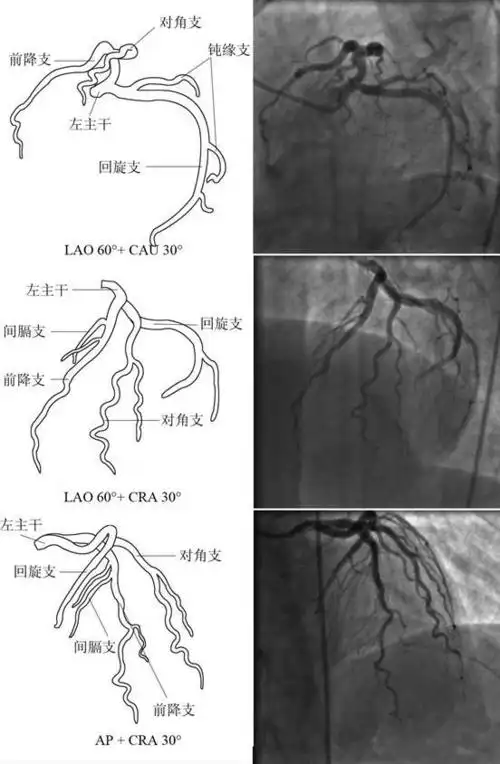

冠脉造影影像解读